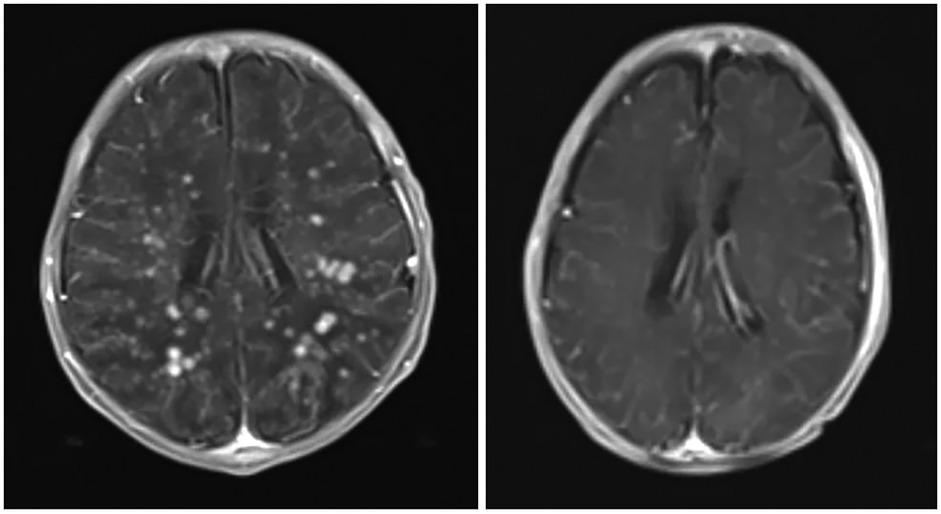

Abstract Background: Although central nervous system fungal infection (CNSF) is uncommon, it is a life-threatening condition that requires prompt diagnosis and management. Here, we report a full-term female neonate with suspected CNSF diagnosed by magnetic resonance imaging (MRI) despite repeatedly negative cerebrospinal fluid (CSF) and blood cultures, in whom the causative pathogen could not be identified. Case presentation: A full-term female neonate presented on the first day of life with irritability, hypoactivity, cyanosis, poor feeding, and two episodes of generalized tonic–clonic seizures with up-rolling of the eyes and lip smacking. Workup for neonatal sepsis showed negative CSF and blood cultures. MRI findings suggested CNSF, and treatment was initiated with low-dose conventional amphotericin B deoxycholate (0.5 mg/kg/day) for 4 weeks, leading to complete clinical and radiological resolution. Conclusion: Negative CSF and blood cultures do not exclude neonatal CNSF. In resource-limited settings, MRI findings together with clinical response to antifungal therapy may support a diagnosis of probable CNSF even when the pathogen is not identified and standard high-dose regimens are not available.